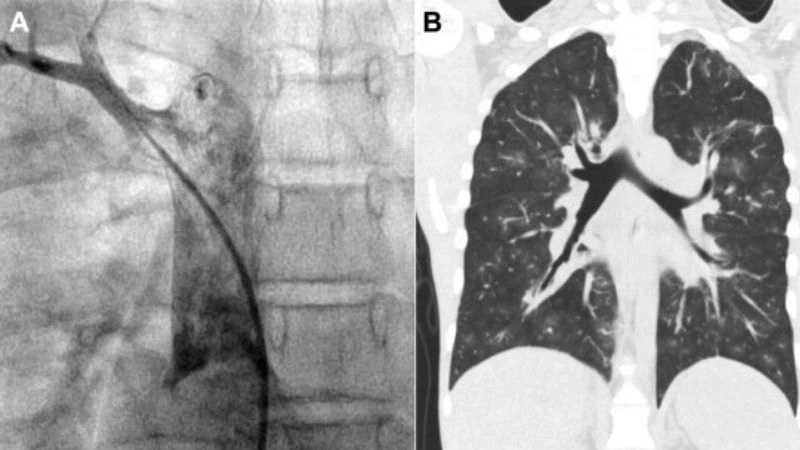

Images visual examples of partial anomalous pulmonary venous return (PAPVR)

Partial anomalous pulmonary venous return (PAPVR) is a rare congenital heart defect in which one or more pulmonary veins drain into the right atrium instead of the left atrium.